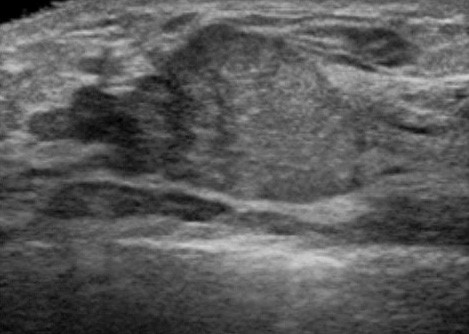

VAB超音波写真

乳腺診療には超音波検査が重要です。しこり、痛みなど乳腺の異常がある場合には診察と乳腺超音波検査を行い、実際にしこり(腫瘍など)があるかどうかを判断します。当クリニックでは富士フイルムヘルスケア社の超音波診断装置を使用しており、高周波プローブによって乳腺の繊細な画像検査が可能です。またリアルタイムエラストグラフィという機能でしこりの硬さを推定することができ、より正確な診断に役立ちます。

超音波検査で観察したしこりが乳がんを疑わず、良性疾患の可能性が高い場合には定期的な超音波検査による経過観察を行います。一方、しこりに悪性の可能性がある場合にはまず穿刺吸引細胞診(FNA:fine needle aspiration)を行います。これは注射に用いる針よりも細い針で乳腺のしこりなどから細胞を吸引し、顕微鏡で診断する検査です。この結果、悪性と判断されれば更なる精密検査を行い、乳がんに対する治療計画を立てていきます。FNAでも良悪性の判定が困難な場合や早期の乳がんが疑われ、ある一定量の組織採取が必要な場合には乳腺針生検を行います。当院ではより正確な診断をおこなうために、吸引をかけて組織を確保しながら針生検を行うVAB(vacuum-assisted breast biopsy)を行っています。FNAもVABも超音波検査で針の方向を確認しながら行います。